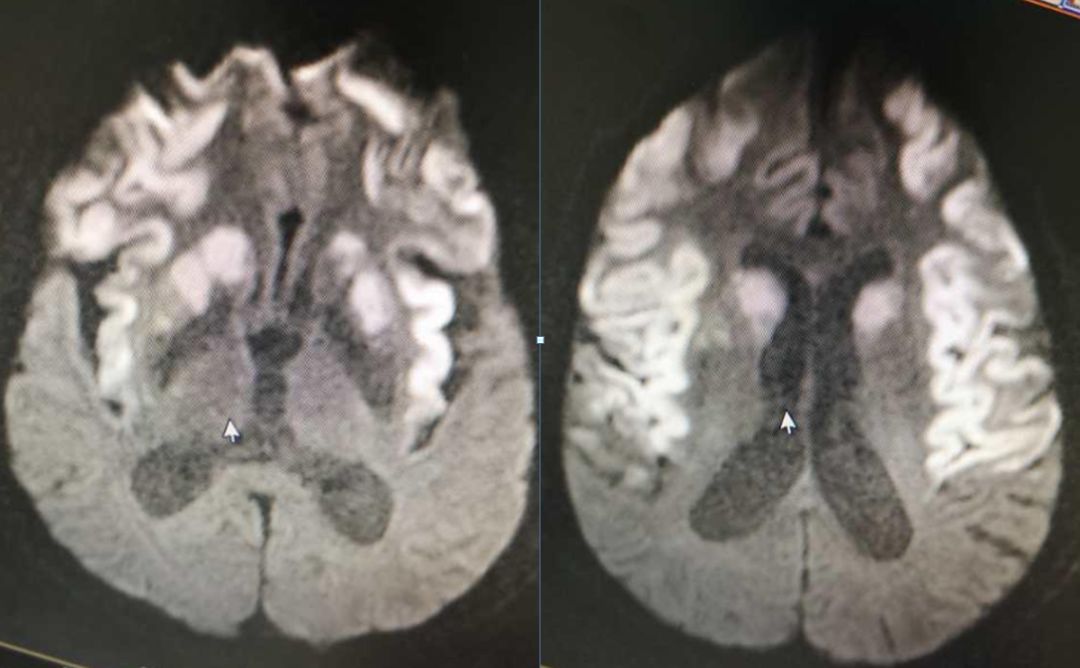

男,29岁,言语不清,协调不良以及行走不平衡3周。

答案:*洛因海**海绵状白质脑病。*洛因海**海绵状白质脑病(heroin spongiform leukoencephalopathy,HSLE)是因烫吸或静脉注射*洛因海**而引起的中枢神经系统器质性疾病。临床和影像特点如下:

1. 有吸*洛因海**史;

2. 急性或亚急性起病;

3. 小脑受损为首发症状,进一步加重可出现锥体系及锥体外系受损表现,甚至昏迷、去皮层状态,但感觉系统不受累;

4. CT和MRI影像显示病灶位于脑白质区,呈广泛、对侧性损害(小脑半球、脑干、内囊后肢、胼胝体压部及大脑半球后2/3),其中小脑受累严重,小脑中线两旁、边界清楚的对侧性类圆形或蝴蝶样病灶最具特点(蝶翼征);在脑干部位,若同时有红核及网状结构受累,则可见“蟹钳征”;在内囊后肢则呈“八字征”。病变在T1W为低信号,T2WI为高信号,FLAIR为高信号,且增强扫描一般无强化.5.病理显示脑白质空泡样变。